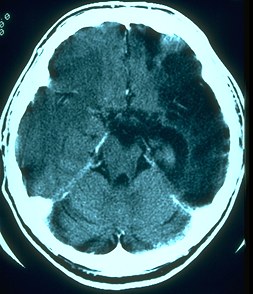

- Computerized Axial Tomography (CAT): Brief x-rays from 180 degrees around head. First used in the 1970s.

- Magnetic Resonance Imaging (MRI): Body tissue is subjected to a strong magnetic field which is turned on and off rapidly in the presence of a radio wave. The atoms of the brain change their alignment (spin) because of the magnetic field when it is on and give off characteristic radio signal when it is turned off. A detector reads those signals and, using a computer, can map the structure of the tissue. Developed in the 1970s and used clinically beginning in the 1980s.